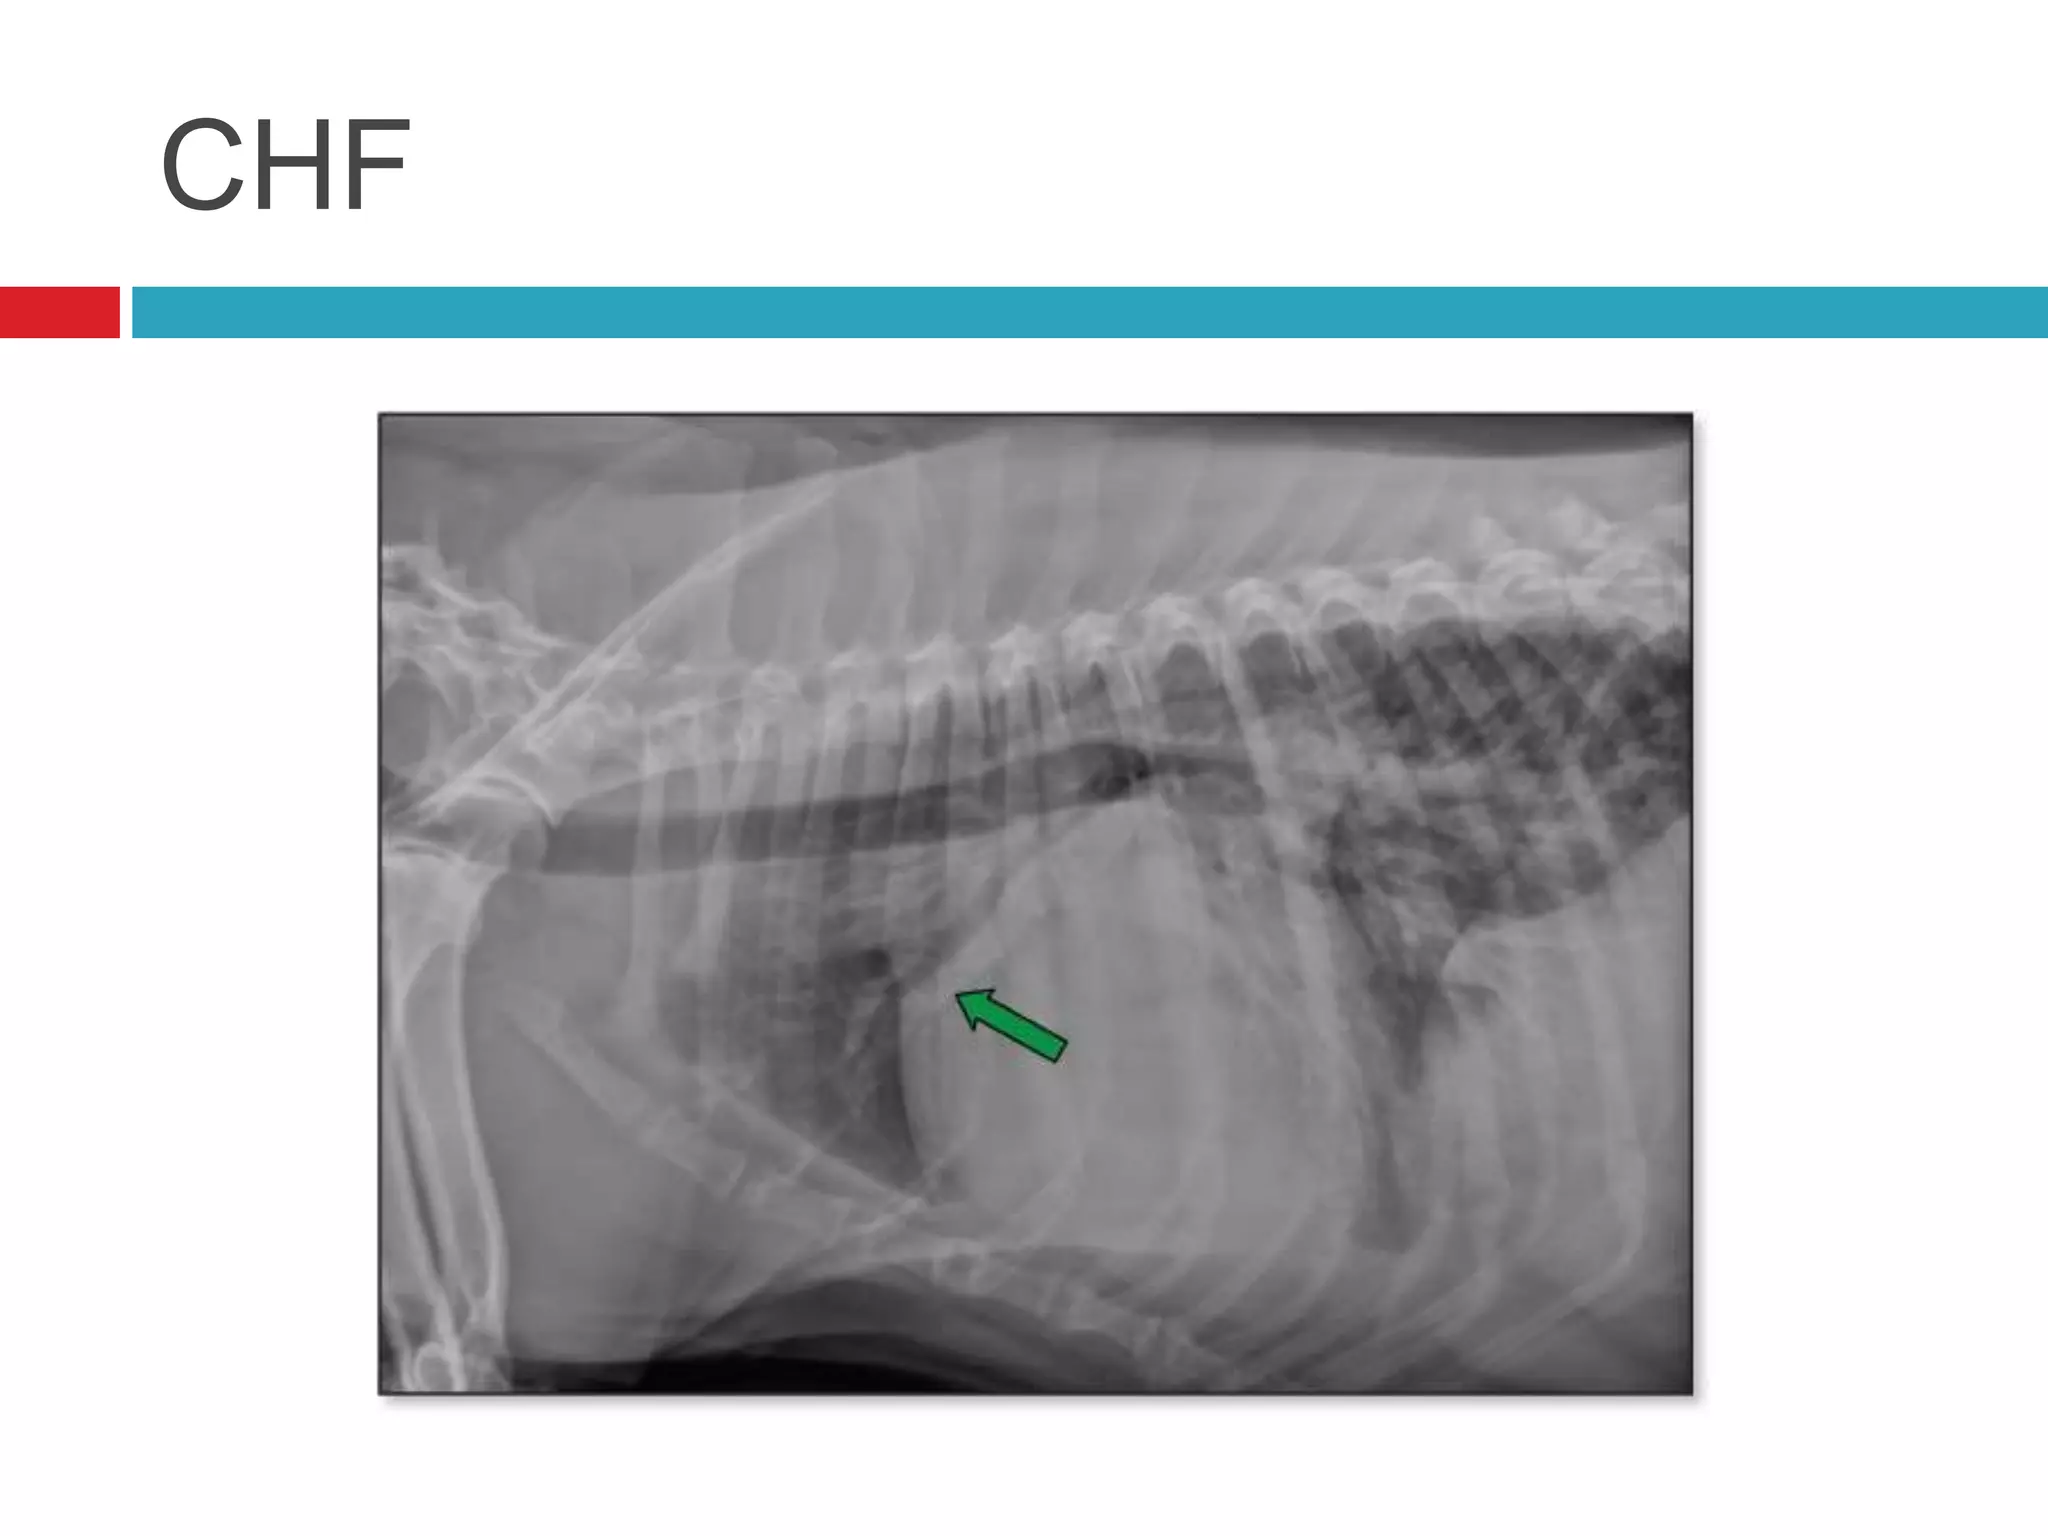

CHF

 Chest rads (needed for diagnosis)

Congestive Heart Failure(CHF)  Left sided  Dyspnea  Pulmonary Edema  Nasal fluid/discharge  Right sided  Dyspnea  Ascites  Jugular Pulses

CHF  Chest rads(needed for diagnosis)